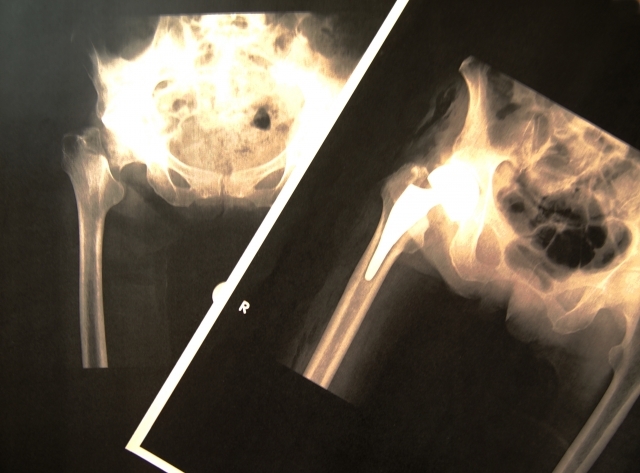

第3章:最初のサインは骨折のこともある

整形外科では、軽いきっかけでの骨折から病気が発覚するケースをよく診ます。以下のサインに心当たりはありませんか?

- 転んだだけで手首を骨折した

第4章:整形外科でできることと考え方

整形外科では骨密度検査を行い、客観的なデータに基づいて対策を検討します。一度検査して終わりではなく、継続的な管理が重要になります。